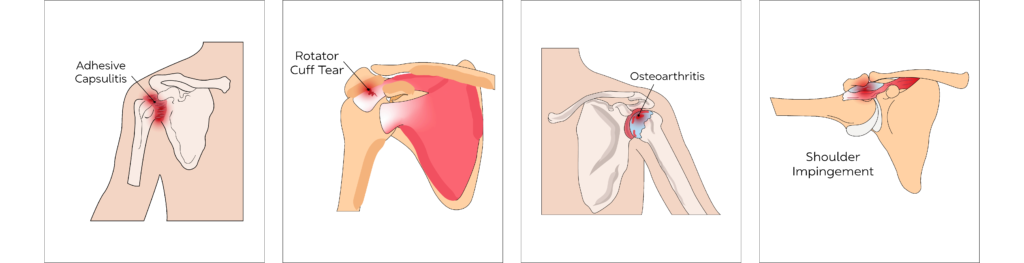

Shoulder Impingement & Bursitis

It includes a wide range of conditions that results in shoulder pain and restricted movements. These include rotator cuff tears (tendon tears), inflamed bursae secondary to tendonitis such as calcific tendonitis or tendonitis due to overuse as in the case of the supraspinatus tendon otherwise known as supraspinatus tendinitis (‘Painful Arc Syndrome’).

Tendonitis including Calcific Tendonitis (General)

Tendonitis is the inflammation of a tendon – the thick cord attaching bones to muscles. In Calcific tendonitis there are calcium deposits within the tendon causing inflammation and swelling and hence pain

Tendonitis can be common in anyone who works in an occupation or sports involving repetitive motion or strain on certain body parts. In the shoulder it mainly affects the supraspinatus tendon. Calcific tendonitis is most common in the 4th and 5th decade of life with 70% of patients being female.

Rotator Cuff Tear

Rotator Cuff is a collective description for four muscles of the shoulder. A rotator cuff tear is a common injury in those who play sports or have repetitive work tasks. It can occur post injury or as a part of the ageing process.

Rotator Cuff Tears are common in adults.

Adhesive Capsulitis - Frozen Shoulder

The covering of shoulder joints known as the capsule gets thickened, inflamed and scarred, which results in pain and restricted movement of the shoulder joint. Pain is usually worse at night affecting sleep and can radiate into the arm and/or neck.

Osteoarthritis

Osteoarthritis is a painful condition affecting any joint with articular cartilage due to gradual wear and tear of the articular cartilage, which protects the bone ends.